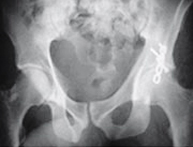

Fracturas de acetábulo

El acetábulo es la concavidad de la pelvis donde se aloja la cabeza del fémur formando con éste la articulación de la cadera. Las fracturas de la cadera por afectación del acetábulo obedecen a traumatismos de alta energía como accidentes de tráfico, deportes de riesgo y precipitaciones desde grandes alturas. Son lesiones complejas y difícilmente valorables con radiología convencional por lo que se requiere estudio mediante tomografía computerizada (TAC) para estimar la gravedad de la lesión y planificar su tratamiento específico.

Luxación de cadera

La luxación de la cadera implica que la cabeza del fémur se desarticula de la pelvis. Su incidencia está muy relacionada con la de los accidentes de tráfico, ya que representa su causa más frecuente. Las luxaciones pueden ser anteriores (15%) o posteriores (85%) y éstas últimas pueden asociarse a una lesión del nervio ciático por compresión. La reducción o recolocación de la cabeza femoral en su lugar debe ser antes de doce horas para impedir la osteonecrosis o muerte de la cabeza femoral por insuficiencia vascular.